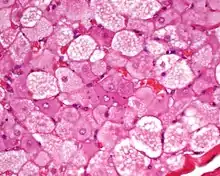

| Micrograph of a hibernoma. H&E stain. | |

The tumors histologically resemble brown fat. There are four histologic types recognized, but one is the most frequently seen (typical). There is a background of rich vascularity.

- Lobular type: Variable degrees of differentiation of uniform, round to oval cells with granular eosinophilic cells with prominent borders, alternating with coarsely multivacuolated fat cells (pale cells). There are usually small centrally placed nuclei without pleomorphism. The cells have large cytoplasmic lipid droplets interspersed throughout.[3][4]